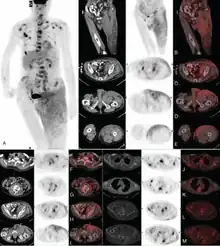

| Extensive Invasive Extramammary Paget Disease | |